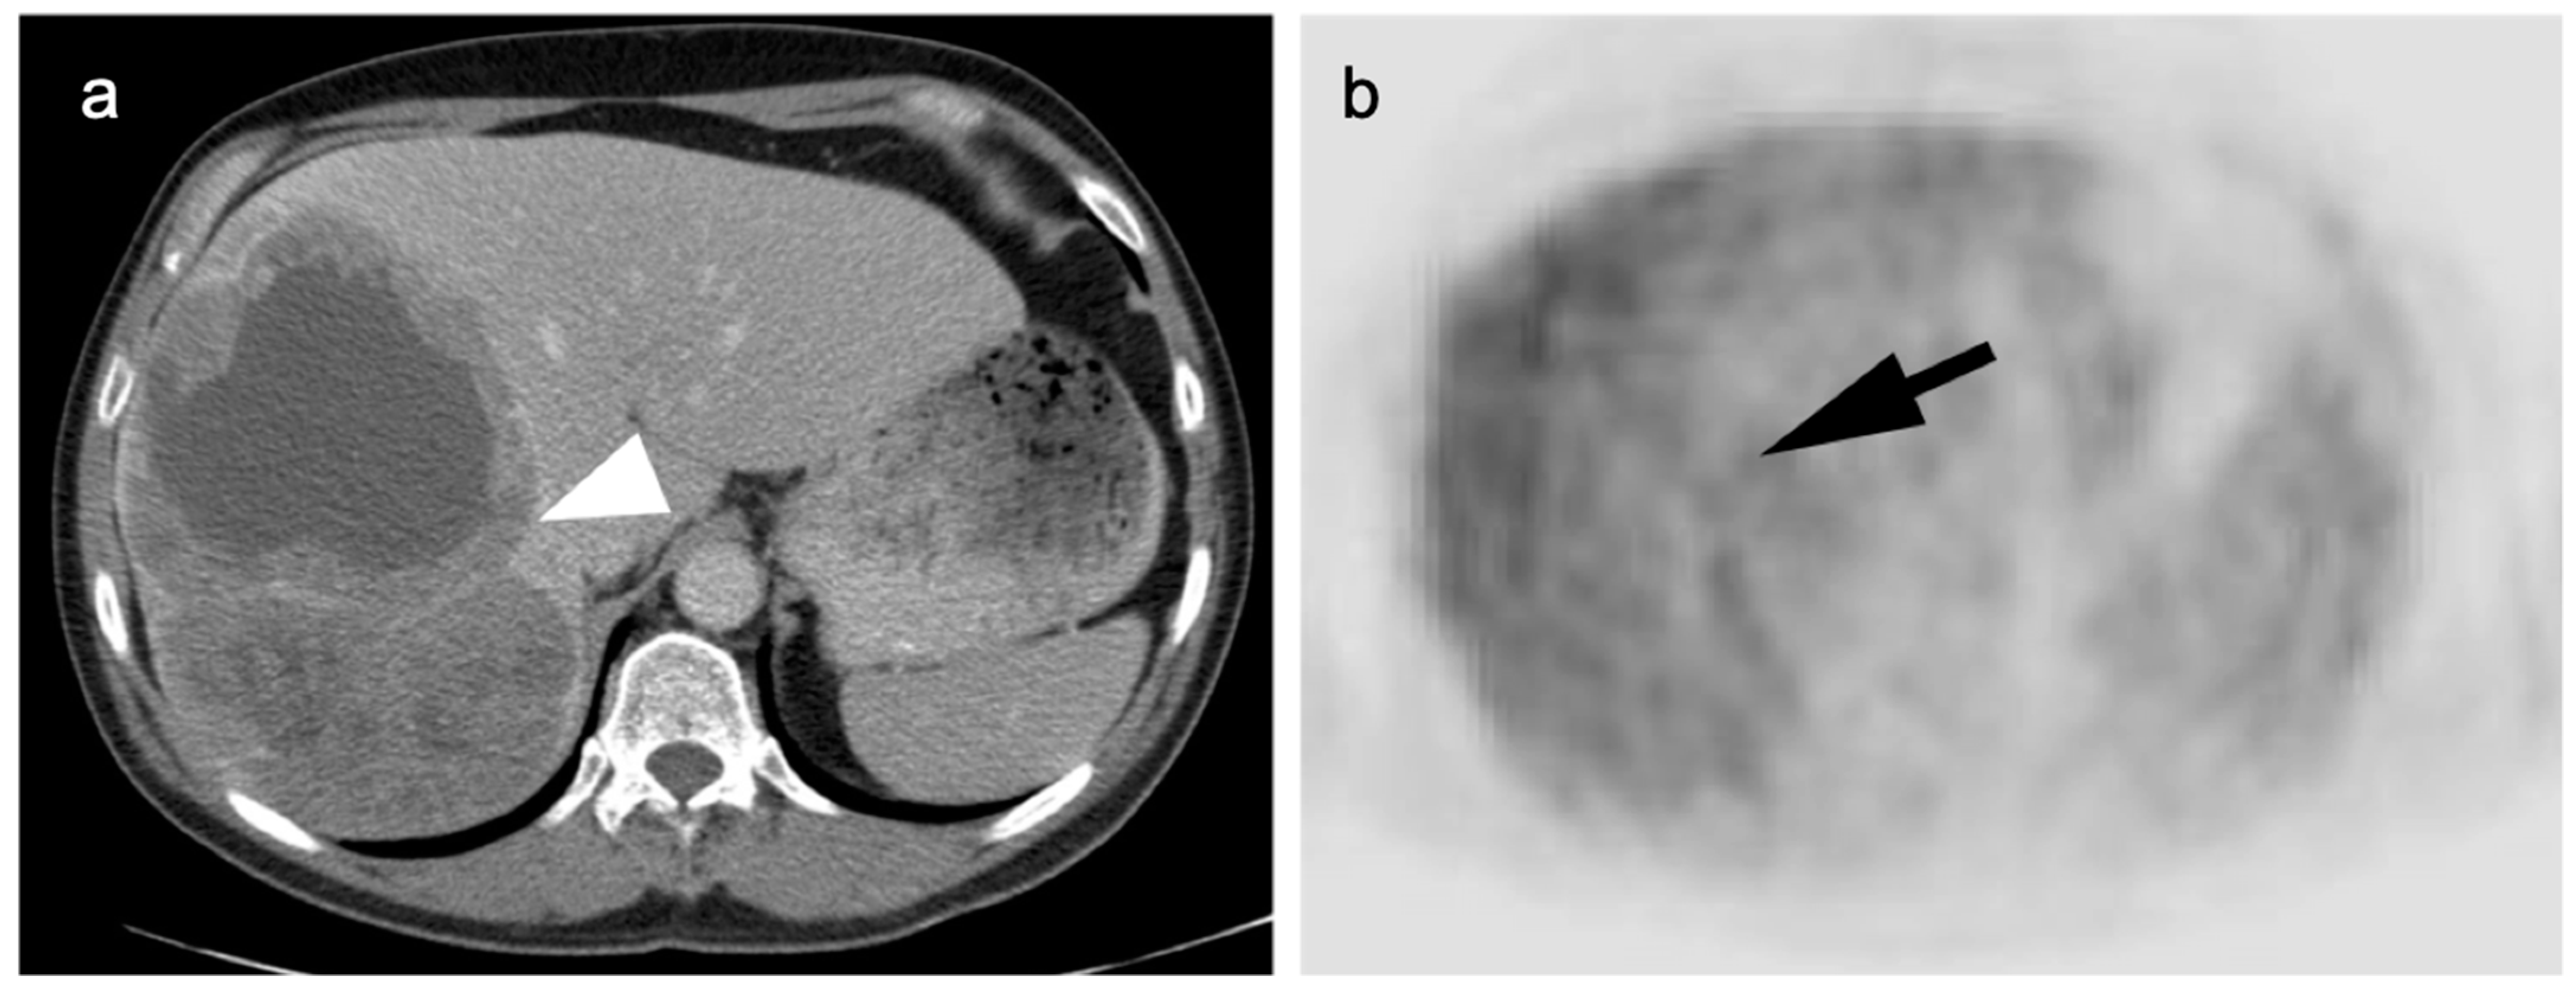

- Ayuso, C.; Rimola, J.; Vilana, R.; Burrel, M.; Darnell, A.; García-Criado, A.; Bianchi, L.; Belmonte, E.; Caparroz, C.; Barrufet, M.; et al. Diagnosis and staging of hepatocellular carcinoma (HCC): Current guidelines. Eur. J. Radiol. 2018, 101, 72–81. [Google Scholar] [CrossRef] [PubMed]

- Talbot, J.N.; Fartoux, L.; Balogova, S.; Nataf, V.; Kerrou, K.; Gutman, F.; Huchet, V.; Ancel, D.; Grange, J.D.; Rosmorduc, O. De-tection of hepatocellular carcinoma with PET/CT: A prospective comparison of 18F-fluorocholine and 18F-FDG in patients with cirrhosis or chronic liver disease. J. Nucl. Med. 2010, 51, 1699–1706. [Google Scholar] [CrossRef] [PubMed]

- Yamamoto, Y.; Nishiyama, Y.; Kameyama, R.; Okano, K.; Kashiwagi, H.; Deguchi, A.; Kaji, M.; Ohkawa, M. Detection of Hepatocellular Carcinoma Using 11C-Choline PET: Comparison with 18F-FDG PET. J. Nucl. Med. 2008, 49, 1245–1248. [Google Scholar] [CrossRef] [PubMed]

- Kesler, M.; Levine, C.; Hershkovitz, D.; Mishani, E.; Menachem, Y.; Lerman, H.; Zohar, Y.; Shibolet, O.; Even-Sapir, E. 68Ga-PSMA is a novel PET-CT tracer for imaging of hepatocellular carcinoma: A prospective pilot study. J. Nucl. Med. 2019, 60, 185–191. [Google Scholar] [CrossRef] [PubMed]

- Thompson, S.M.; Suman, G.; Torbenson, M.S.; Chen, Z.E.; Jondal, D.E.; Patra, A.; Ehman, E.C.; Andrews, J.C.; Fleming, C.J.; Welch, B.T.; et al. PSMA as a Theranostic Target in Hepato-cellular Carcinoma: Immunohistochemistry and 68 Ga-PSMA-11 PET Using Cyclotron-Produced 68 Ga. Hepatol Commun. 2021, 6, 1172–1185. [Google Scholar] [CrossRef]

- Gündoğan, C.; Ergül, N.; Çakır, M.S.; Kılıçkesmez, Ö.; Gürsu, R.U.; Aksoy, T.; Çermik, T.F. 68Ga-PSMA PET/CT Versus 18F-FDG PET/CT for Imaging of Hepatocellular Carcinoma. Mol. Imaging Radionucl. Ther. 2021, 30, 79–85. [Google Scholar] [CrossRef]

- Hirmas, N.; Leyh, C.; Sraieb, M.; Barbato, F.; Schaarschmidt, B.M.; Umutlu, L.; Nader, M.; Wedemeyer, H.; Ferdinandus, J.; Rischpler, C.; et al. 68Ga-PSMA-11 PET/CT Improves Tumor Detection and Impacts Management in Patients with Hepatocellular Carcinoma. J. Nucl. Med. 2021, 62, 1235–1241. [Google Scholar] [CrossRef]